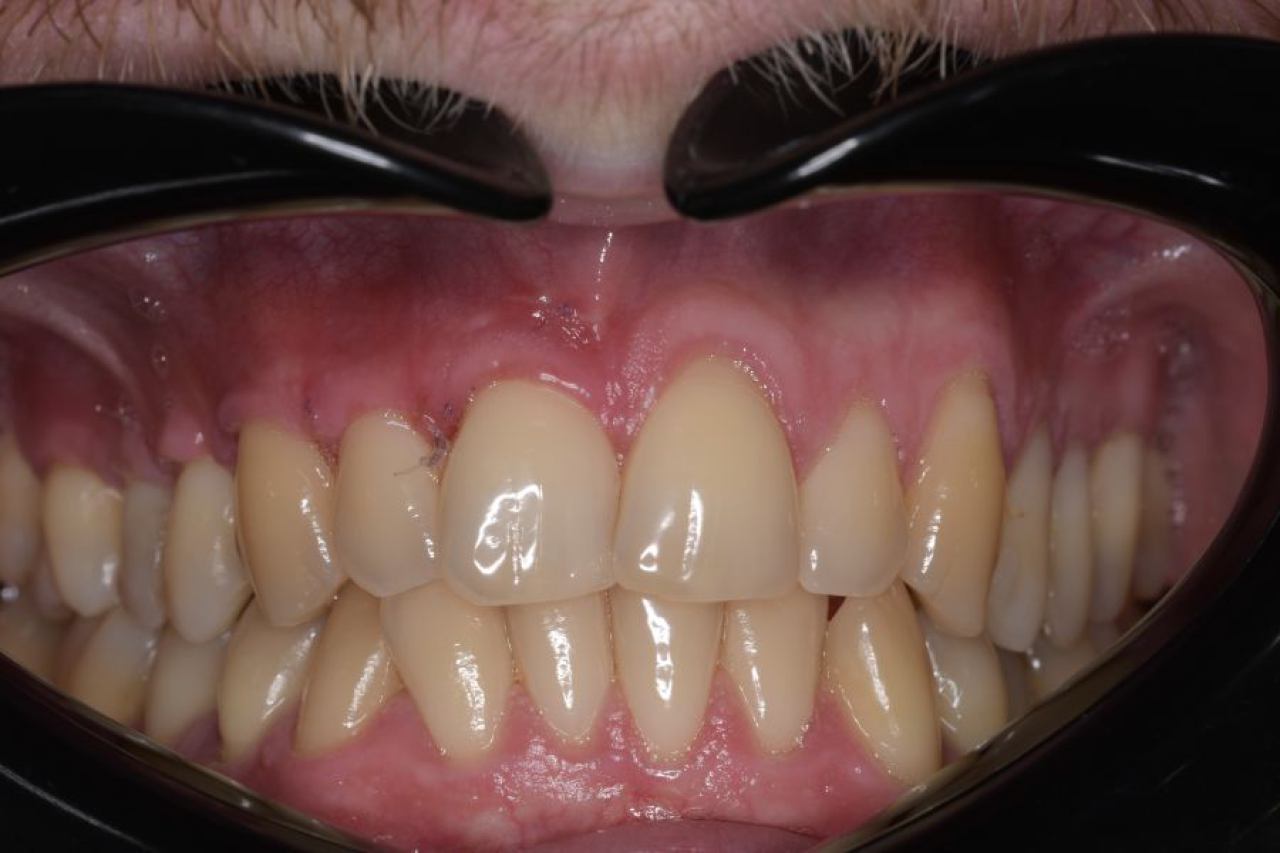

Parodontologija i kirurgija

Parodontologija je grana dentalne medicine koja se bavi zdravljem potpornih struktura zuba (parodonta). Parodont se sastoji od zubnog mesa (gingiva), kosti i vlakana koja vežu zub za kost (parodontalni ligament).

Ovo je grana kojoj Marković Dental Clinic pridaje puno pažnje jer je vrlo kompleksna i bitna za cijelo oralno zdravlje.

Regeneracija kosti i mekog tkiva

Gingivalne recesije u narodu poznatije kao „povlačenje zubnog mesa" moguće je korigirati kirurškim zahvatom te vratiti gingivu (zubno meso) u fiziološki položaj mikrokirurškim tehnikama. Zahvati koje odrađujemo kod regeneracije kosti i mekog tkiva su podizanje dna sinusa (sinus lift) i nadomještanje izgubljenog volumena kosti (augmentacija kosti, regeneracija kosti).